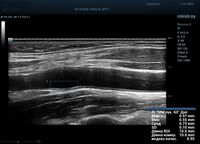

На сегодняшний день измерение IMT происходит автоматическим путем при использовании функции AUTO-IMT. Необходимо указать прибору зону интереса, стандартной длиной (1 см), в которой происходит отслеживание кромок и выдача максимального, среднего и минимального значения. УЗИ аппараты компании Mindray среднего, экспертного и премиального класса снабжены данной функцией и позволяют контролировать не только полученные значения, но и оценить точность измерения кромки в конкретной зоне по индексу качества. Используя индекс качества, легко решить, можно ли использовать полученное значение.

Форма отчета стала удобной: в единой таблице сводятся измерения левых и правых артерий, указываются все значения с автоматическим расчетом общего среднего показателя. Если один из показателей измерения резко выбивается и считается недостоверным – его можно исключить из расчета.